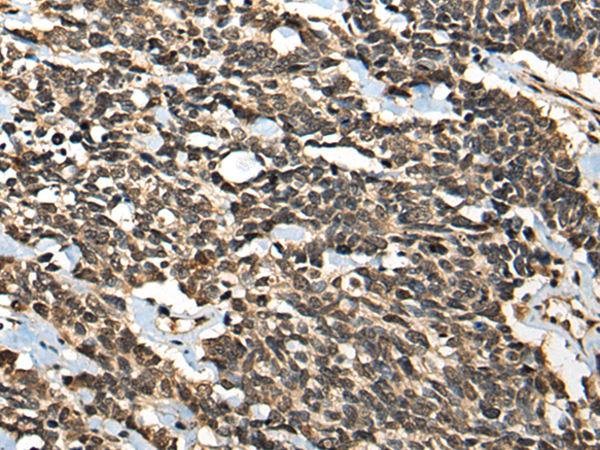

IHC positive control: |

Human lung cancer and human prostate cancer |

IHC Recommend dilution: |

30-150 |